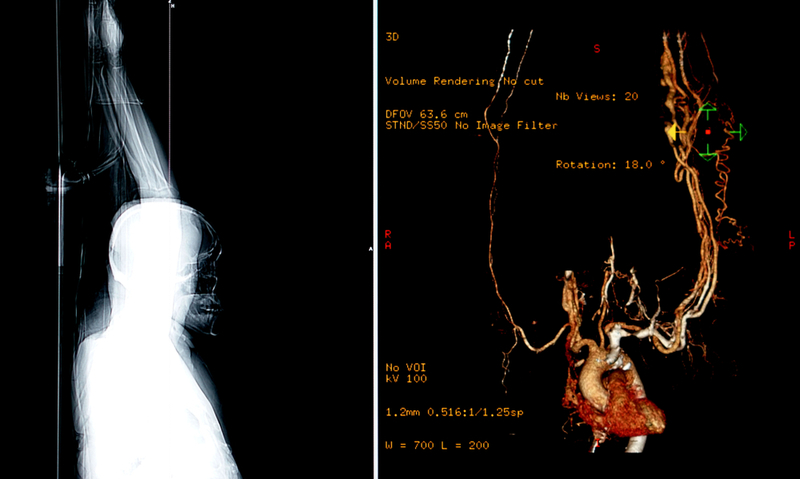

Patients with chest pain are initially assessed with coronary computed tomography angiography (CTA), a non-invasive scan that determines the degree of artery narrowing (stenosis), which is expressed as a percentage. An invasive technique called fractional flow reserve (FFR) then assesses whether the stenosis is obstructing blood flow (called ischaemia). FFR involves inserting a pressure wire into the artery then calculating the ratio between the maximum blood flow in the narrowed artery and the maximum blood flow in a normal artery.

A new non-invasive technique for assessing ischaemia uses anatomic information from standard coronary CTA scans and applies a mathematical algorithm simulating blood flow to calculate FFR. Several clinical trials have shown that this method, called FFRCT, accurately reflects invasively measured FFR. However, there is little information on clinical outcomes using coronary CTA followed by FFRCT to decide treatment.